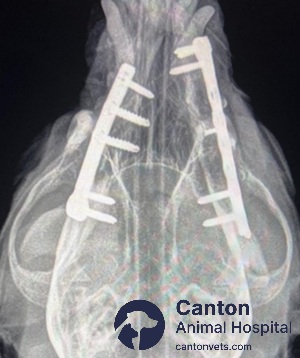

Bone plating: Small titanium or stainless-steel plates are surgically attached to the bone with screws to secure unstable or high-stress fractures.

Radiographs (X-rays): Capture detailed images of the jawbone and teeth to locate fractures and evaluate severity.